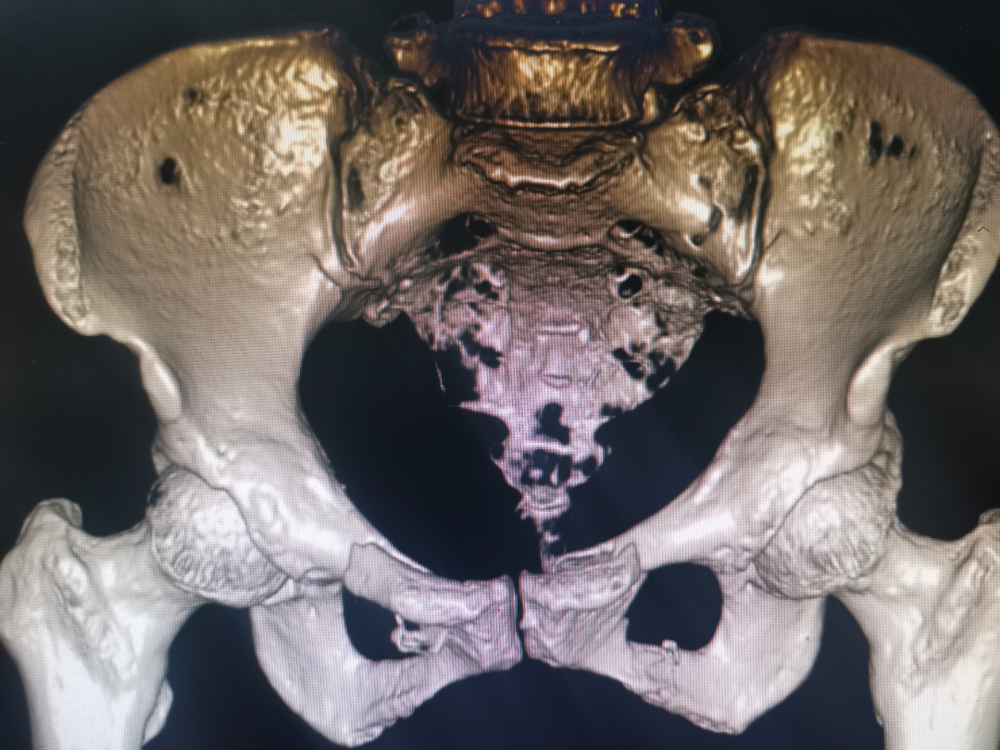

患者葉女士,因不慎摔倒導致(zhì)全身多處疼痛入院,完善檢查顯示雙側恥骨(gǔ)上下肢骨折,骨盆前環不穩(wěn)定。對(duì)於骨盆(pén)前環骨折的治療,保(bǎo)守治療需長期臥(wò)床,易導致褥瘡、肺部感染、泌尿係感染及深靜(jìng)脈血栓風險;傳統開放複位鋼板(bǎn)內固(gù)定術式手術切口大、手術時間長,同時存在膀胱的醫源性損傷風險。尤其對於肥胖患者,外固定架及其它內(nèi)固定術(shù)式比較困難,風險相對較大,且會給患者(zhě)的生活帶來極大不便。

我院骨科團隊高度重(chóng)視葉某某的治療,經充分術前準備,由董明(míng)副(fù)主任、葉強醫師為患者在全(quán)麻(má)下行“經皮骨盆前(qián)環改良椎弓根釘-棒內固定術(shù)INFIX技術”,僅用不到(dào)1小時便成(chéng)功(gōng)完成了手術,僅2個3cm的手(shǒu)術切口,出血量約20ml,術(shù)後第二天患者就可以床上翻(fān)身及坐起,功能恢複良好。